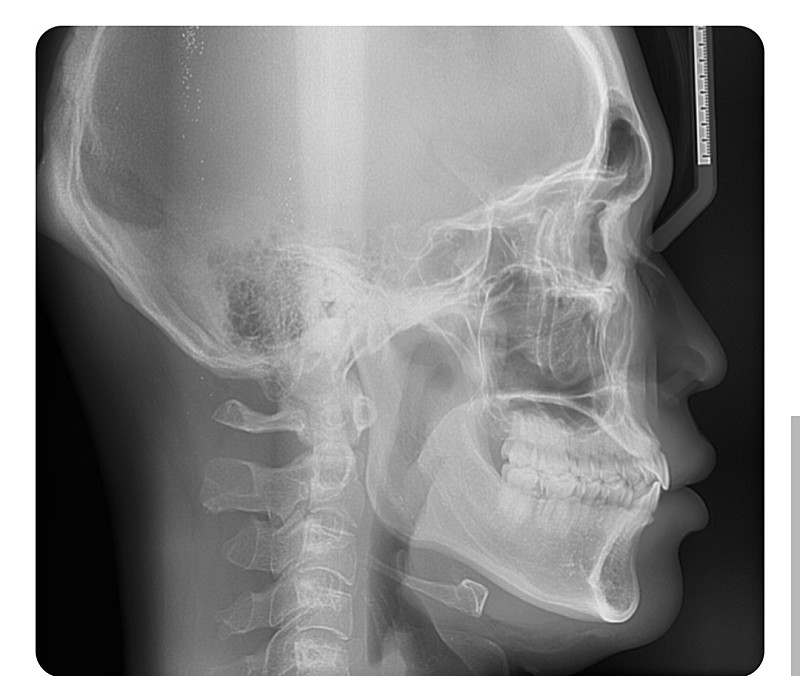

1.상악이나 하악이 정상범주에서 벗어났나요?

3.정상범주 판단기준이 뭔가요? 교합이 맞으면 정상범주내라고 보나요?

1. 상악과 하악을 비교했을 때, 상악 저성장으로 보입니다. 다만 정확한 것은 교정치과 방문 후 상담이 필요합니다.

3. 단순 교합 뿐만 아니라 상악과 하악골의 관계를 파악하게 되며 여러가지 계측점이 있습니다. 치과의사 선생님이나 교정선생님에 따라 계측점이 다르므로 현재 치료하시는 치과 방문 후 선생님과 상담이 필요합니다.